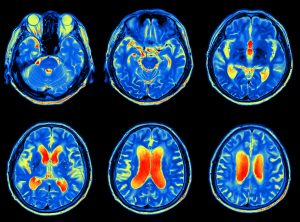

shutterstock 468738953The Center for Disease Control (CDC), estimates that each year over 20 million children and adults will suffer from concussions, mild traumatic brain injuries (TBI), or head trauma as a result of sports injury, falls, motor vehicle accidents and blunt force trauma. Head impact injuries cause disruption of participation in sports, work, and recreational or just everyday activities. Symptoms associated with head impact trauma may include: dizziness, nausea, blurred or double vision, imbalance, hypersensitivity to light, and cognitive impairment.